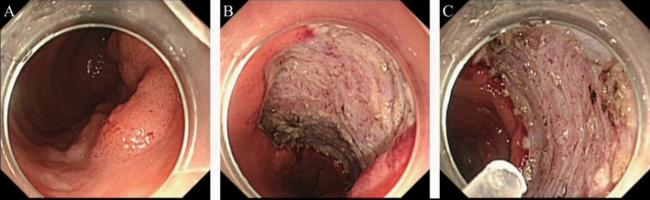

3.针对大肠ESD术后止血的应用

针对EMR较难完整切除的大肠肿瘤,选择ESD切除的技术日趋成熟,如何预防术中及术后出血仍然是重要问题。患者男,76岁,直肠肿瘤,ESD术后使用复合微孔多聚糖止血粉止血成功,见图3

图3 大肠ESD术后止血

A:行ESD术的直肠环肠腔二分之一大小约5.0 cm×6.0 cm侧向发育型肿物;B:ESD术后创面以复合微孔多聚糖止血粉外敷;C:术后无迟发性出血